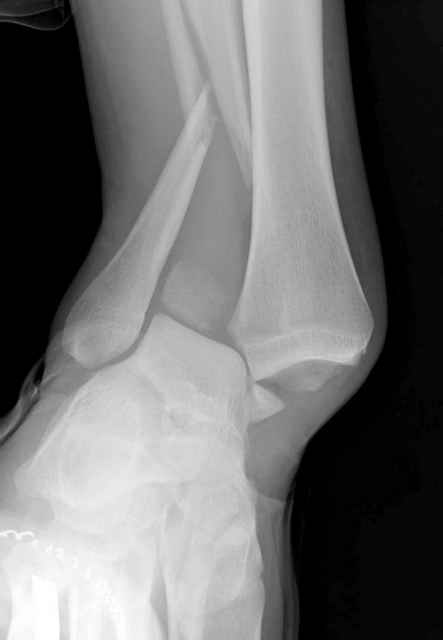

Конечно, компьютерный томограф более информативный метод, но с помощью недорогого обычного стандартного в нейтральном положении стопы: прямого, бокового и косой (ankle mortise) ренгенологического метода можно получить полную информацию о повреждении голеностопного сустава, а сравнительный снимок с другой стороны подтвердить наличие повреждения.

При реконструкции голеностопа, о важности восстановления длины малоберцовой для профилактики пост травматического артроза разбирали в предыдущих дискуссиях. Нарушенную биомеханику голеностопа без восстановления длины малоберцовой, не восстановить только швом медиальной связки.

Расширенная медиальная щель более чем на 4 мм и укорочение малоберцовой более чем 2 мм, а перелом заднего края большеберцовой смещения более 2мм с вовлечением 30% поверхности сустава, считается отходом от нормы голеностопного сустава, и подлежит к оперативному вмещательству.

Здесь похожий случай трехнедельной давности, перелом почти сросся и была укорочена малоберцовая, на операции длину малоберцовой смогли восстановить только после того, когда проксимальнее пластины ввели шуруп и использовали его как толкатель, с помощбю дистракционого инструмента (lamina spreader).

Меньше всего волнует положение медиальной лодыжки - в любое время можно провести остео или реостеосинтез, при несращении можно просто резецировать без ущерба для движений в голеностопе. Здесь обошлись фиксацией одним 4 мм канюлированным шурупом.